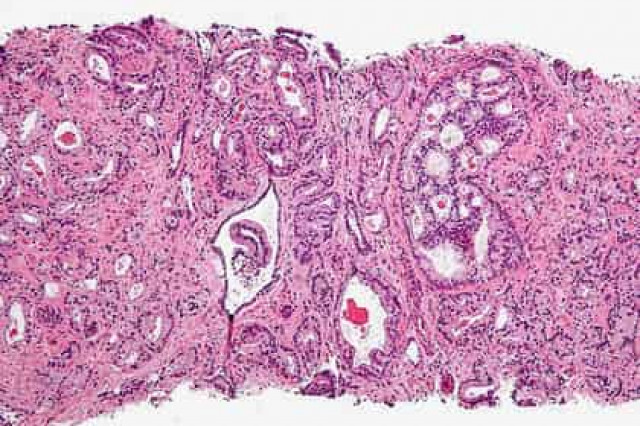

Ученые Университета Кардиффа (Великобритания) обнаружили мутацию, которая способствует развитию агрессивной формы злокачественных опухолей, называемой кастрационно-резистентным раком предстательной железы.

Исследователи выяснили, что мутация, затрагивающая ген PIK3CA в клетках предстательной железы, способствует развитию агрессивной формы новообразования. PIK3CA кодирует белок, являющийся субъединицей фермента фосфоинозитид-3-киназы (PI3K), участвующего в процессе роста, деления клеток и их ухода от апоптоза (программируемой клеточной гибели). Другой ген PTEN отвечает за блокирование активности PI3K, и мутации в нем также вызывают развитие опухолей.